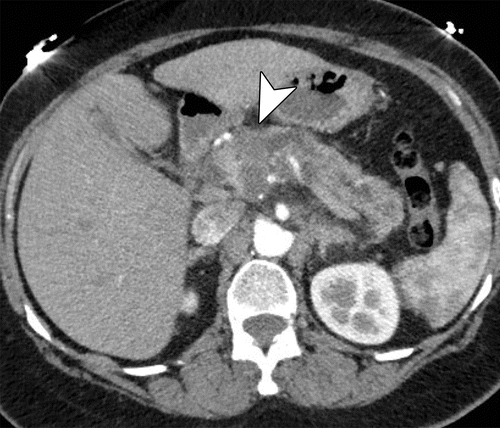

- tomografia com cortes finos para pâncreas com protocolo trifásico observa massa heterogênea, hipocontrastante em relação ao pâncreas ao redor, atrofia da glândula e dilatação do ducto de wirsung e hepatocolédoco. Ela permite estadiamento para avaliar a invasão de vasos importantes como artéria mesentérica, tronco celíaco, veia mesentérica-porta; além de gânglios linfáticos e metástases hepáticas (fígado) ou peritônio;

- tomografia e ressonância. Como os PNETS são altamente vascularizados costumam se apresentar como tumores hipercontrastantes após administração de contraste na fase arterial apresentando coloração mais clara que o pâncreas ao redor tanto na tomografia quanto ressonância. Também pode ser realizados: o Octreoscan (Cintilografia com receptores para Octreotide) e a Cintilografia com Gálio 67;

Metastases são raras e correspondem a 2 % de todos canceres pancreáticos oriundas do câncer colorretal, pulmões, mama e melanoma. A maioria é assintomática e é descoberta por exame de imagem. Em geral, são altamente vascularizados costumam se apresentar como tumores hipercontrastantes após administração de contraste na fase arterial apresentando coloração mais clara que o pâncreas ao redor tanto na tomografia quanto ressonância. A biopsia por eco-endoscopia com punção pode dar diagnóstico, mas não é necessária na lesão isolada.